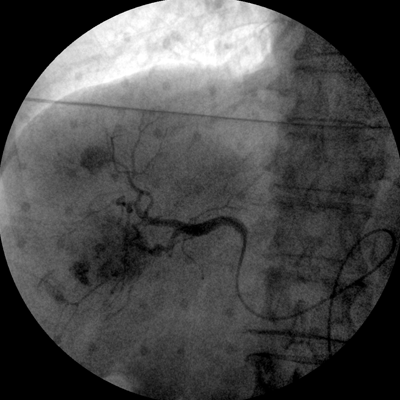

Clinical picture

臨床圖片